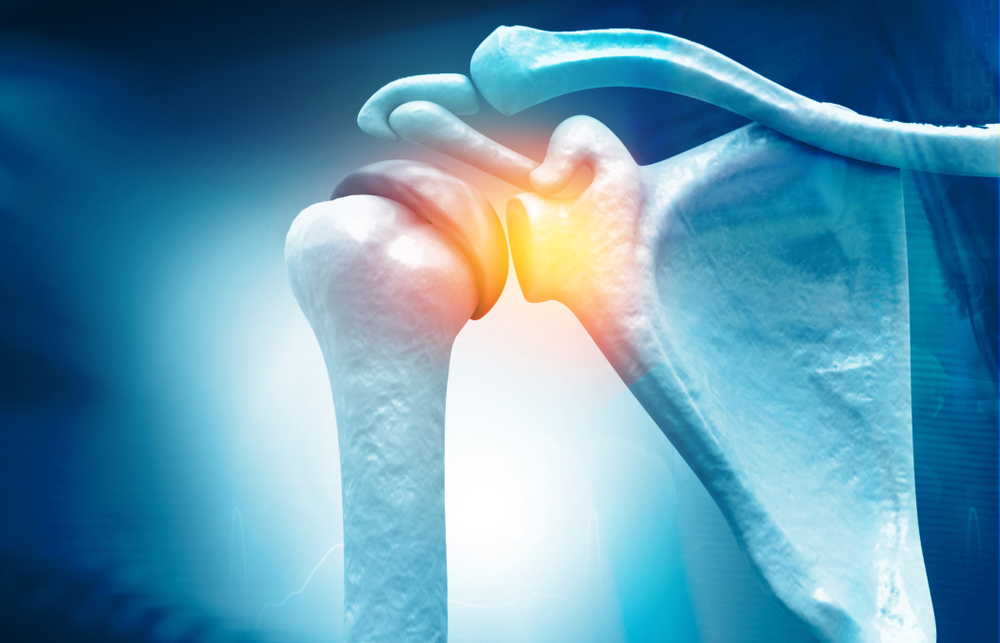

¿Qué es la Artroscopia de Hombro?

La artroscopia de rodilla es un procedimiento quirúrgico mediante el cual se introduce una cámara muy pequeña en la articulación del hombro del paciente para examinar o reparar los tejidos dentro o alrededor de la misma.

La artroscopia de hombro se puede recomendar para los siguientes problemas:

lesión de slap (Labrum Superior del Hombro)

lesión de bankart

tendón del bíceps dañado o roto

lesión de manguito rotador

espolón óseo roto o inflamación alrededor del manguito rotador.

inflamación o daño en el el revestimiento de la articulación (generalmente causado por artritis reumatoide).

artritis del extremo de la clavícula

tejido suelto

síndrome de pinzamiento del hombro.